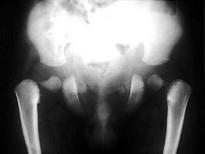

男,2岁,发育迟缓,头颅软,结合图像,最可能的诊断是?(?)A.成骨不全B.颅锁骨发育不全C.马方综合征D.软骨发育不全E.黏多糖病

问题 男,2岁,发育迟缓,头颅软,结合图像,最可能的诊断是?(?)

选项 A.成骨不全 B.颅锁骨发育不全 C.马方综合征 D.软骨发育不全 E.黏多糖病

答案 B